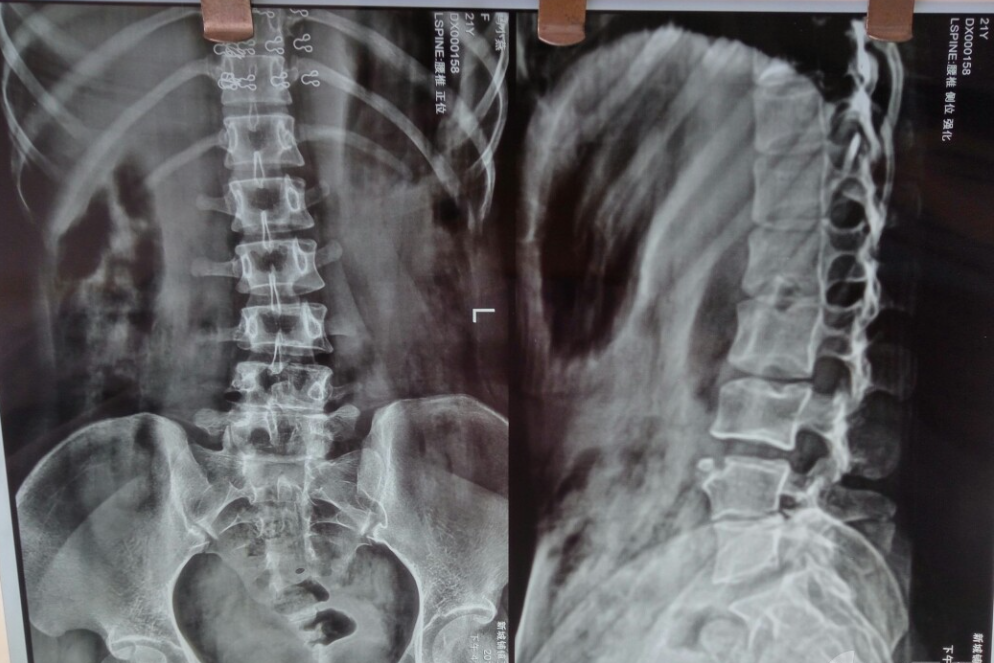

①腰椎X片(腰椎正侧位片、动力位片等)

图片 31